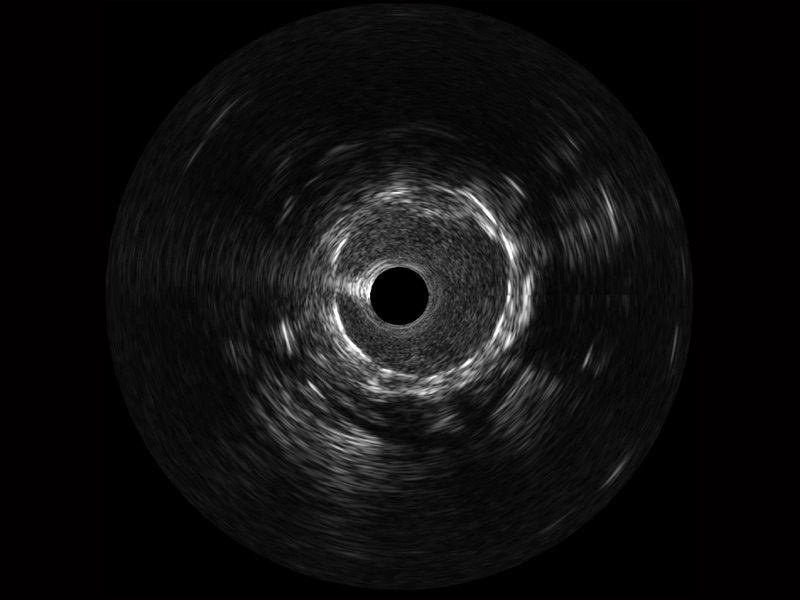

玖鼎集团宽频IVUS图像

对比传统IVUS导管成像,玖鼎集团宽频IVUS图像的近场支架梁显影更细腻,远场中膜外血管仍清晰可辨,兼顾远中近,兼顾分辨力与穿透深度